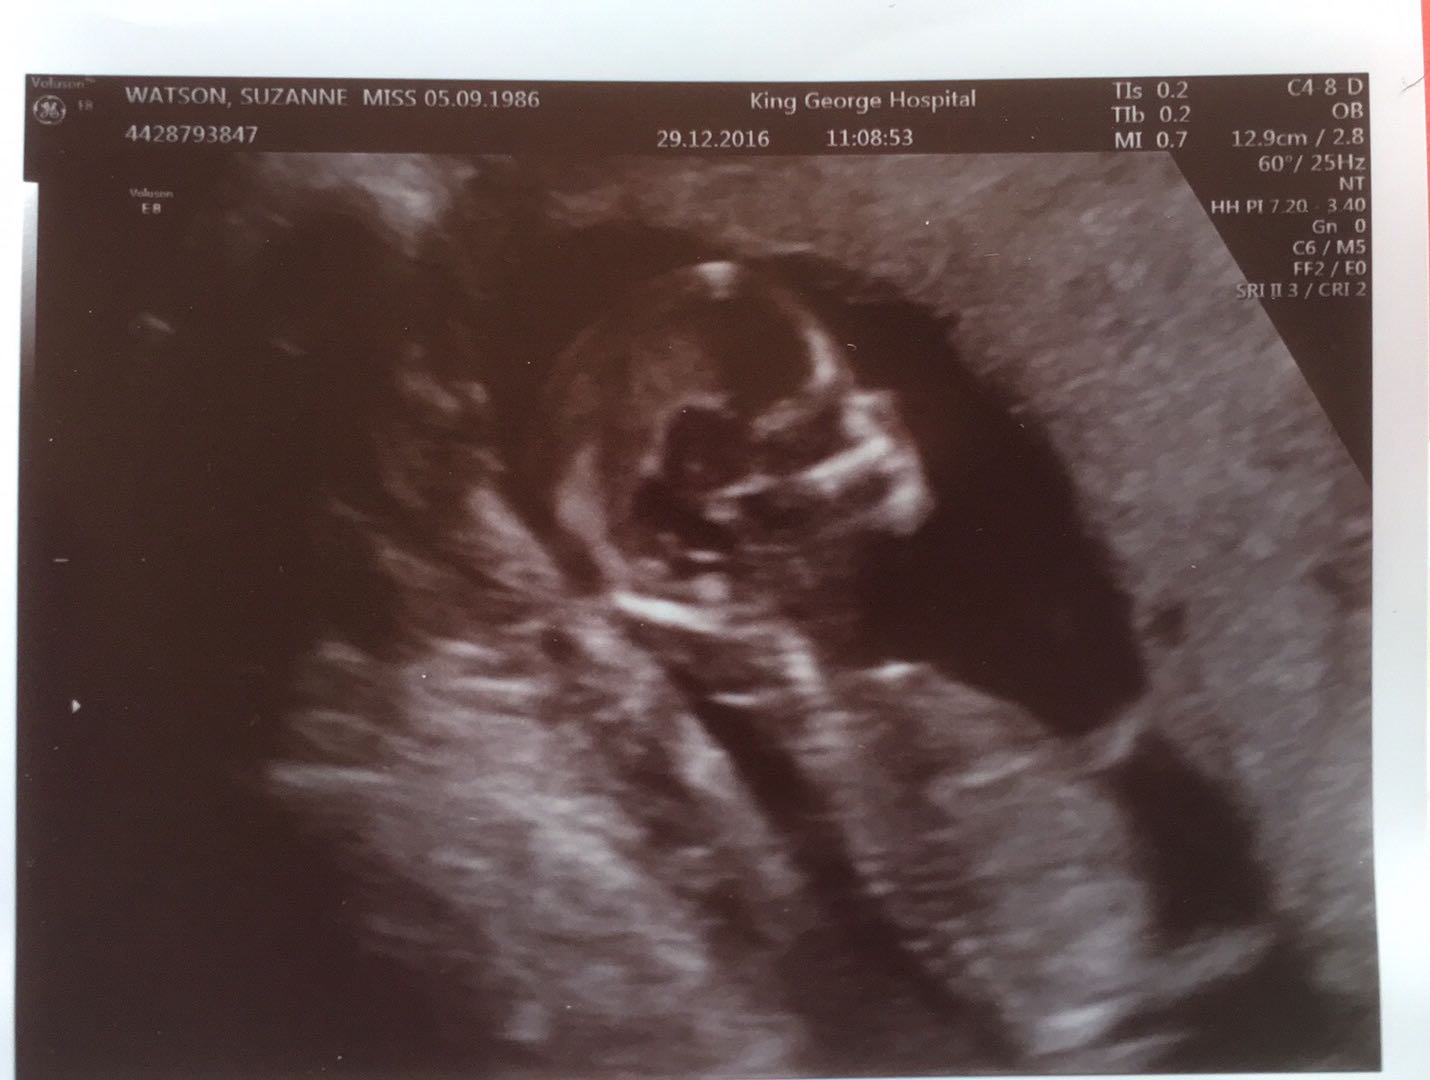

I'm interested to find out what people think the gender may be of my baby?

Not sure that the scan helps but I'm just interested in what people think.

I have no knowledge on the skull theory but im pretty good at guessing nubs but i dont see any nub here cause legs are in the way :( you have any other pics?

No nub, more pics?

Then I'll give you a boy skull guess just for fun (not reliable!!)